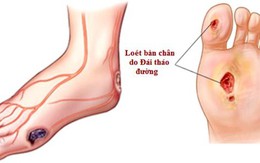

NSND Anh Tú qua đời vì bệnh tiểu đường, đây là 5 biến chứng nguy hiểm ít ngờ tới của căn bệnh này

20/12/2018 15:22

Biến chứng mạn tính của bệnh tiểu đường xảy ra như một phần tất yếu trong quá trình phát triển của bệnh. Và đó cũng chính là nguyên nhân dẫn đến tử vong của các bệnh nhân.